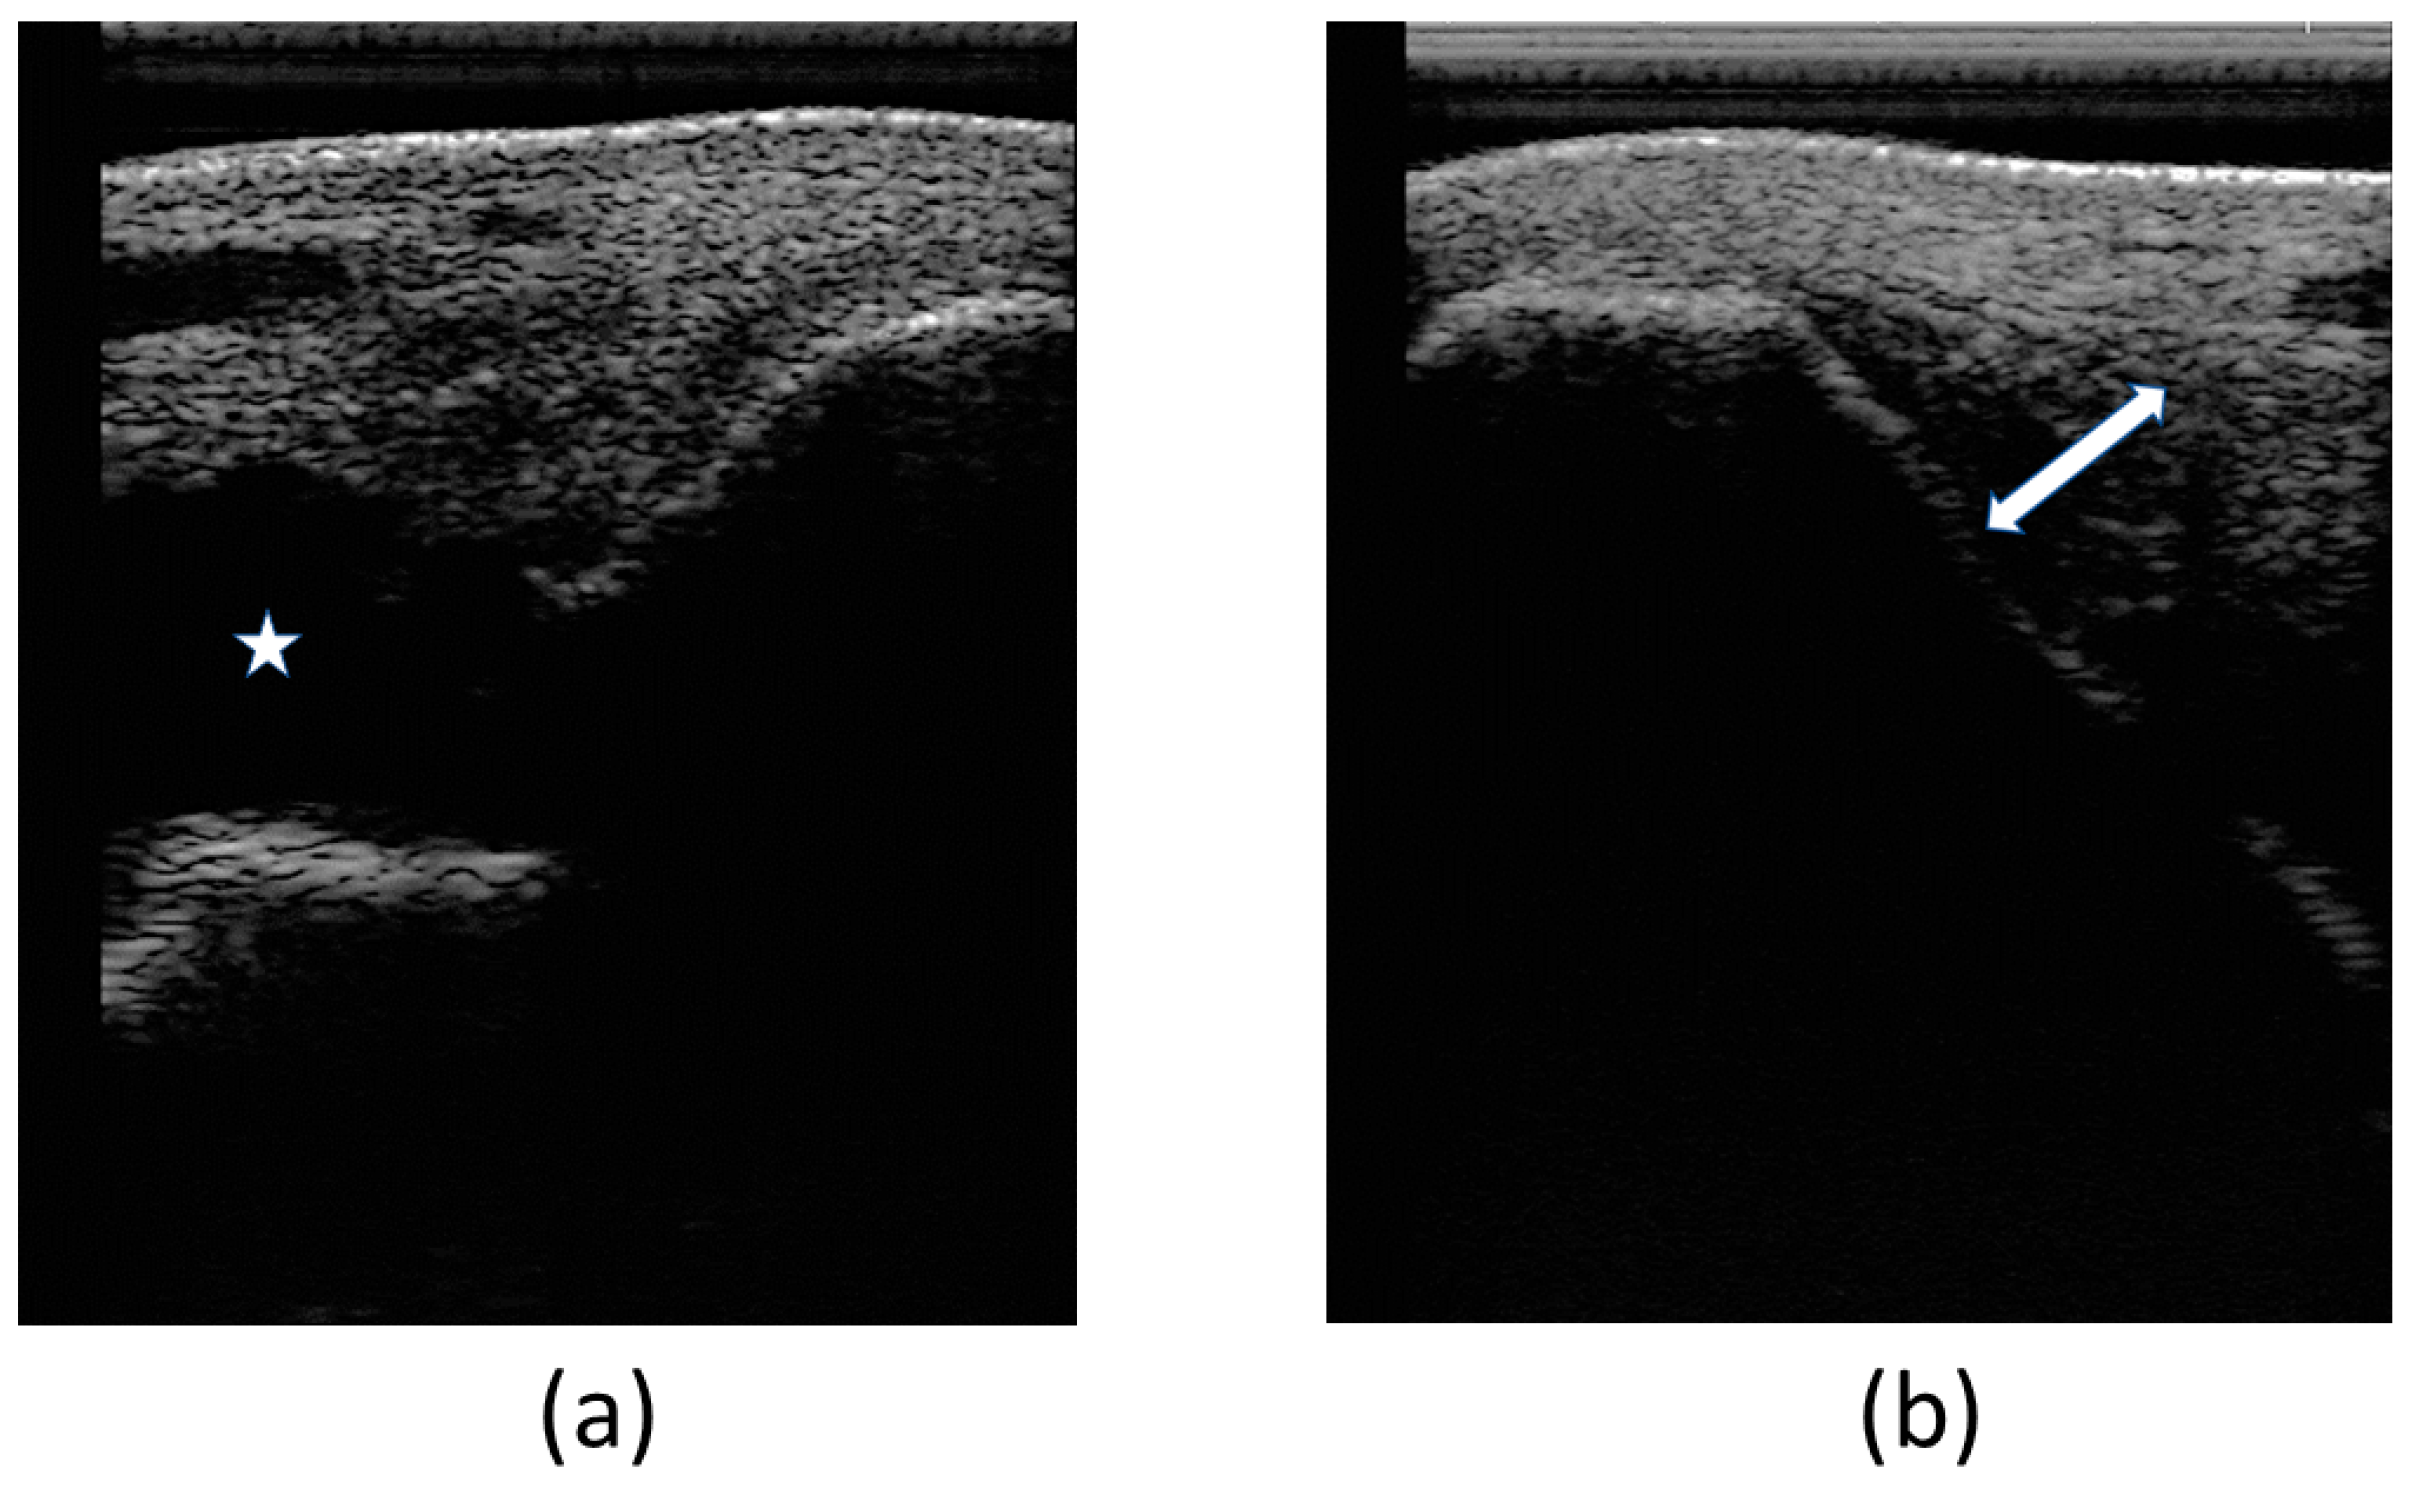

3.2.2. Ultrasound Examination

At the first veterinary assessment, ultrasonographic examination evidenced an increased amount of hypoechoic fluid containing areas of increased swirling (heterogeneous echogenicity) (Figure 4a), suggestive of an organized hematoma and/or fibrin within the joint—hemarthrosis. Also evidenced was a moderate fiber pattern disruption of LMCL (hypoechoic region) at medial malleolus insertion as well as an increased cross-sectional area (Figure 4b). Cartilage surface was normal.

Figure 4.

Images of the first ultrasonographic examination. Desmitis of LMCL insertion at the medial malleolus: (a) increased amount of hypoechoic fluid within the joint, signaled with the star (*); (b) disruption of the fibers at the insertion, signaled with the double arrow (↔).